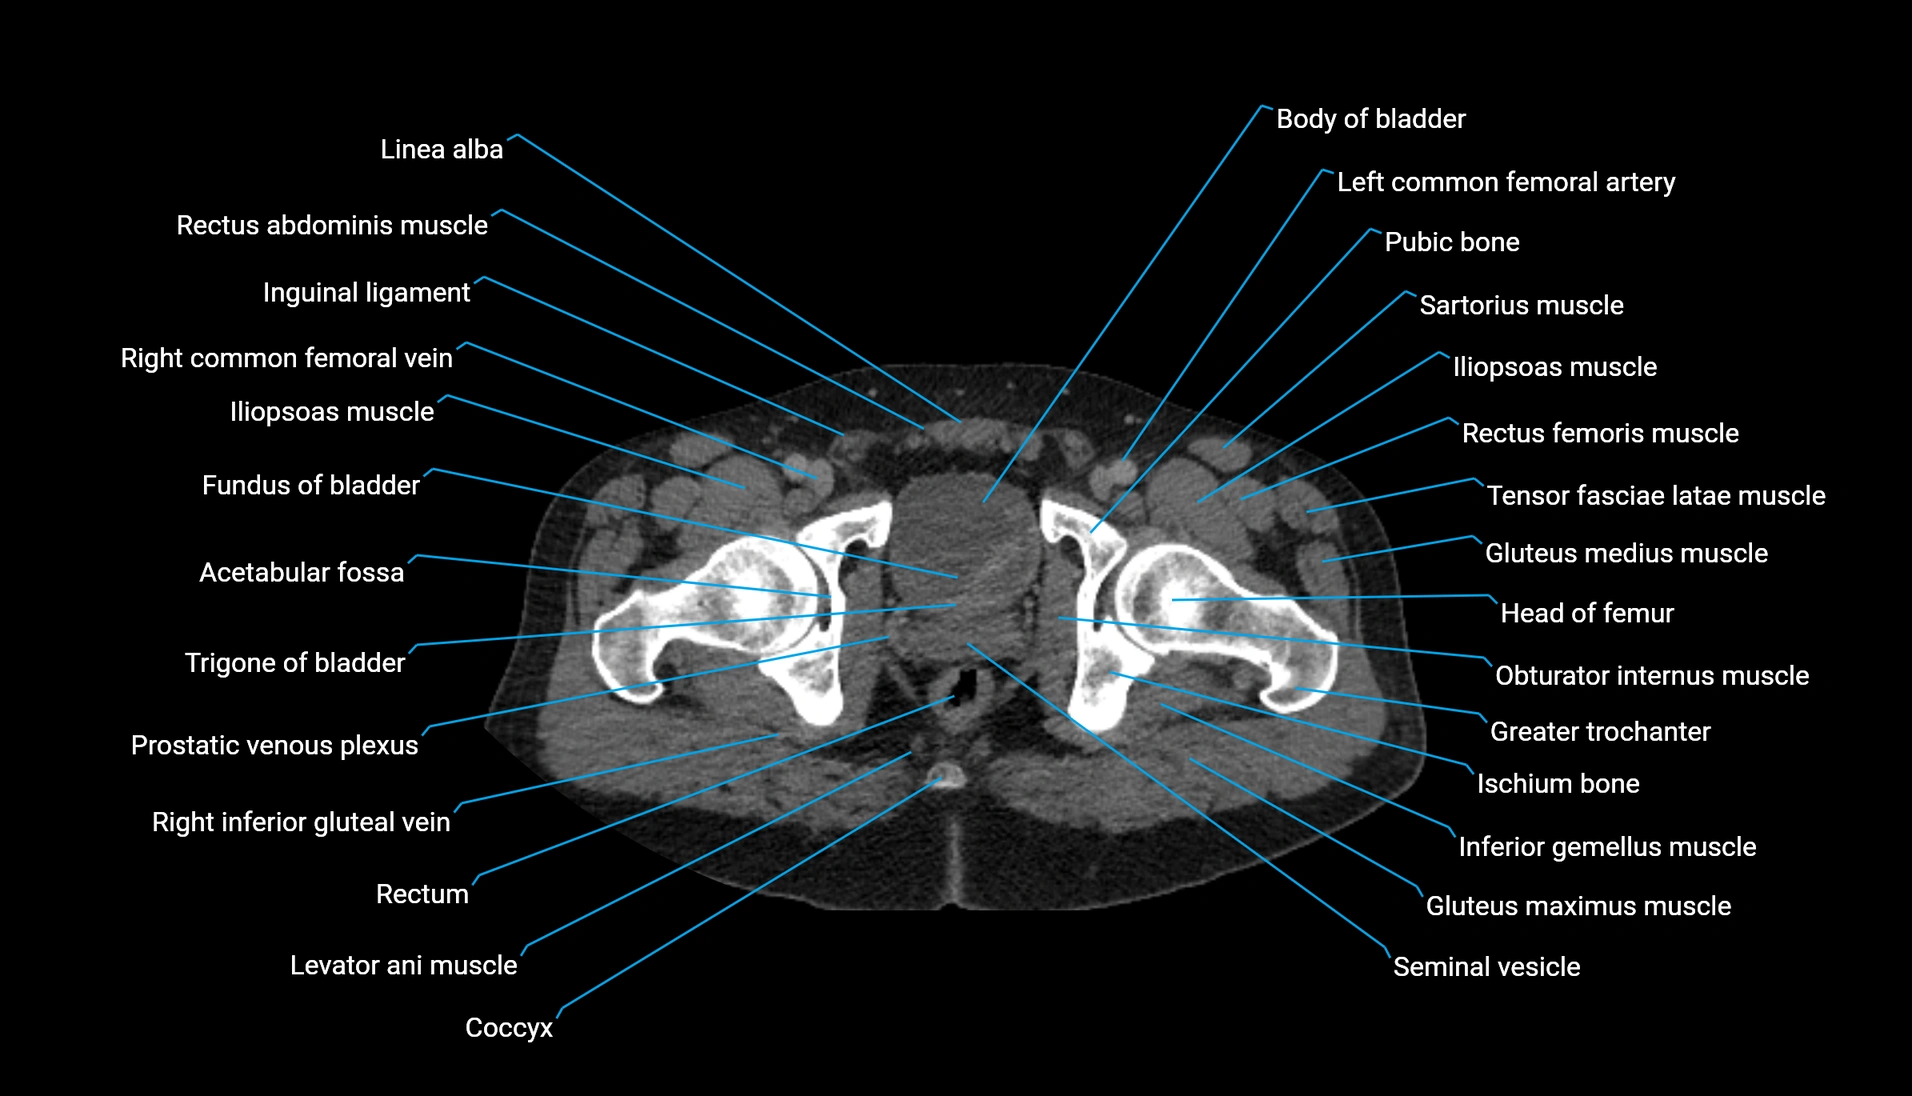

CT Appearance

Non-contrast CT:

-

Demonstrates cortical bone of acetabular rim in excellent detail

Detects fractures, dysplasia, retroversion, or bony overcoverage (pincer impingement)

3D reconstructions used in preoperative hip surgery planning

CT VRT 3D image

CT image